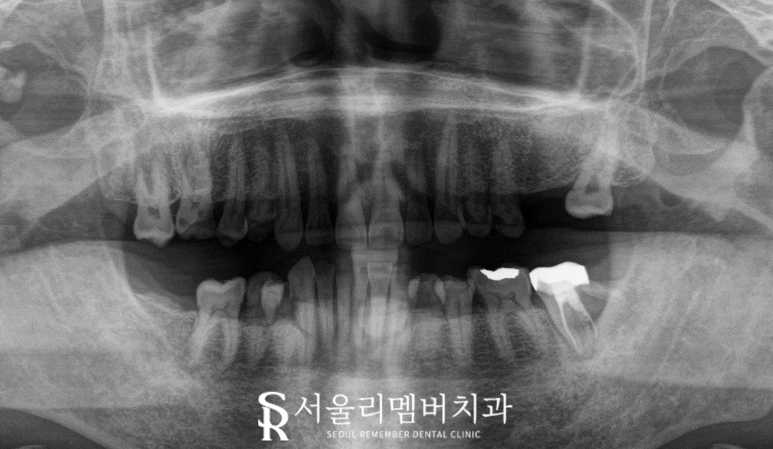

서울대입구역 치과 에서 보여드리는 구내 사진을 보면

구치부가 상실되거나 치열이 틀어져 있고,

2025.01.07

일부 치아는 깨져있거나

심한 충치가 존재했습니다.

정면에서 볼 때 제일 눈에 띄는 특징은

심한 과개 교합(deep bite)이었는데요,

윗니가 아랫니의 대부분을 덮어

아랫니가 거의 보이지 않는 상태였으며

이는 정상 관계에서 크게 벗어난 모습이라

할 수 있습니다.